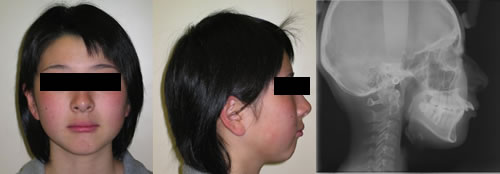

Krankeは来院当時14才の女性で上顎前歯の前突改善のために来院する。

大臼歯の関係は1級である。

1.初診時 顔面